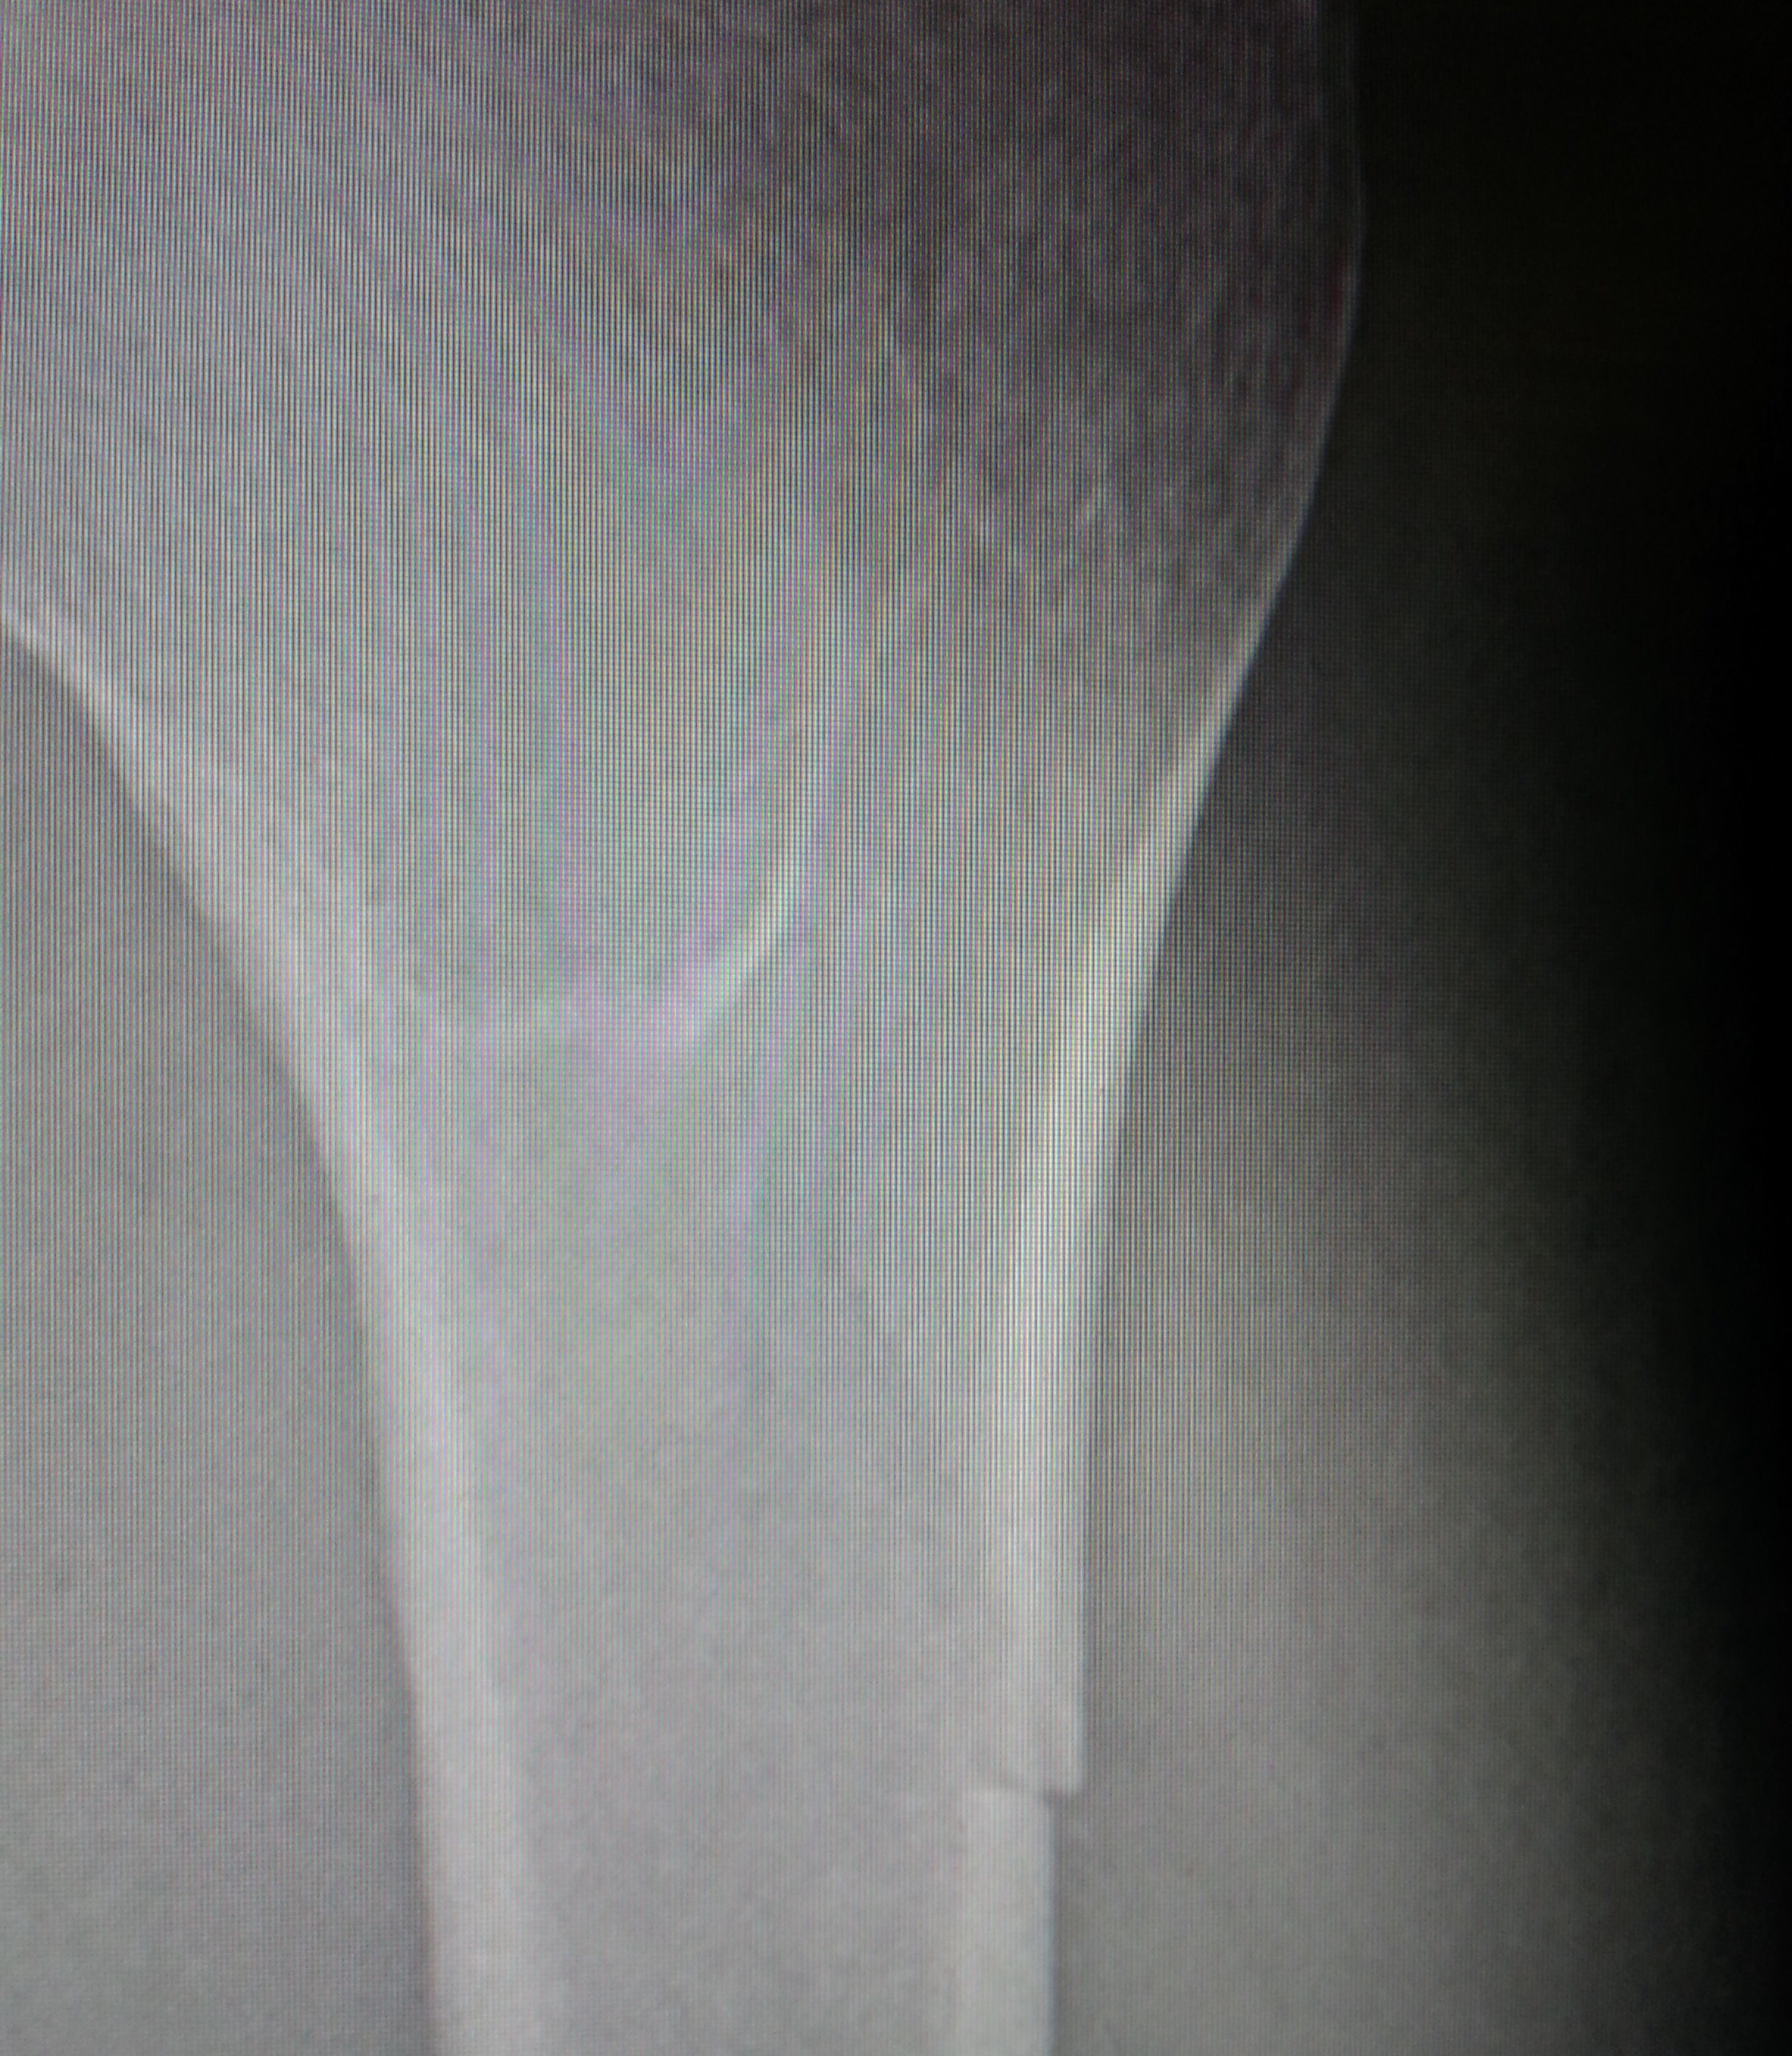

Back home, A&E done, fracture and break found and clearly seen, it’s back to the fracture clinic on Tuesday.